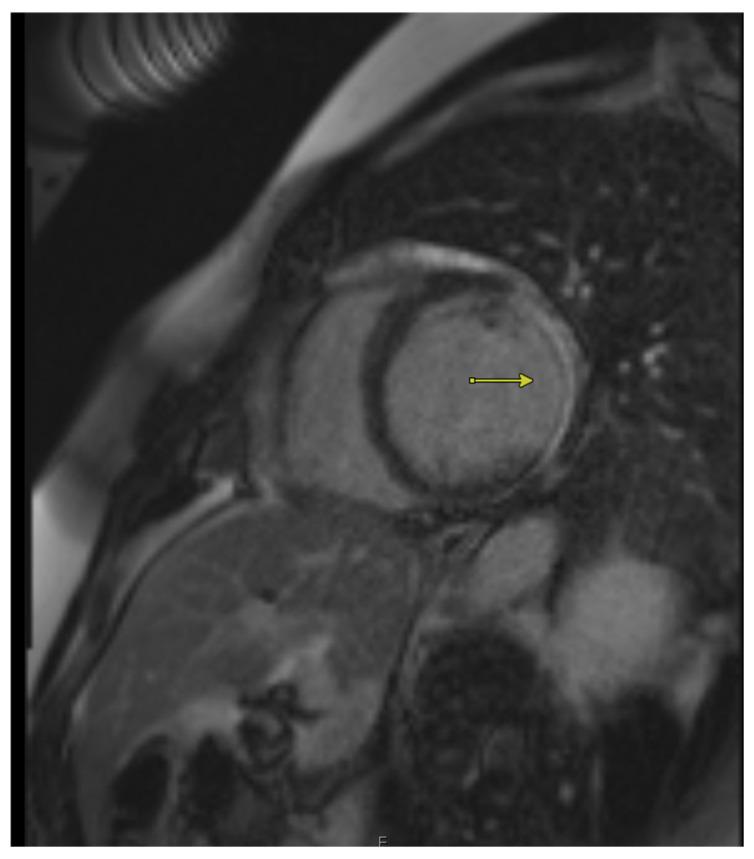

The Role of Imaging Modalities in Estimating Myocardial Viability: A Narrative Review.

Myocardial viability assessment plays a critical role in the clinical management of patients with ischemic heart disease, particularly in guiding revascularization decisions. Various non-invasive imaging modalities have been developed and refined to evaluate viable myocardium, each offering unique insights into myocardial perfusion, metabolism, and contractile function. This review examines the comparative strengths and limitations of key imaging techniques. Understanding the pathophysiological basis and diagnostic capabilities of these modalities enables clinicians to tailor viability assessments to individual patient profiles, ultimately enhancing decision-making and optimizing outcomes in ischemic cardiomyopathy.